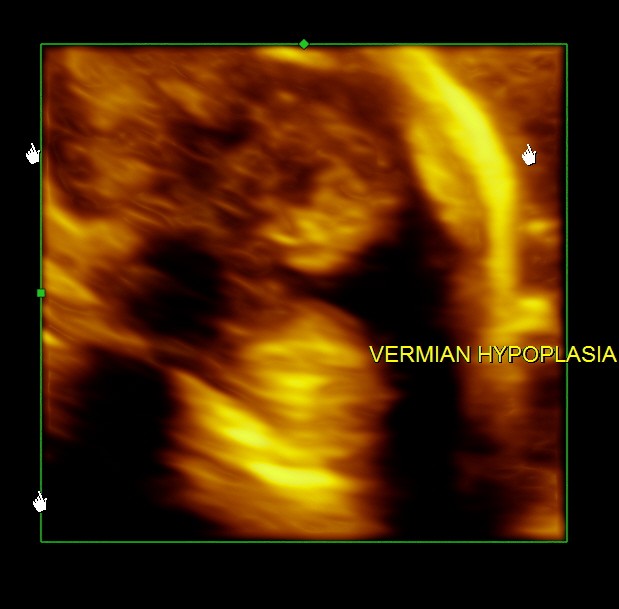

Ultrasound pictures of the fetal cranium are given below and showed cerebellar vermian dysgenesis .The buttocks sign can be appreciated.